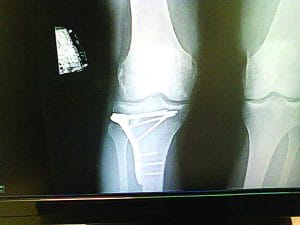

I just came back from an extreme hernia repair. I’ve had two meniscus repairs and one meniscus removal—all on the right knee. I have turf toe. I have nuggets of cauliflower ear. I can’t throw a football with my right arm because it feels like my elbow will fall apart. I have a weak lower back. My right shoulder clicks. My fingers are morphing into knots. I’ve broken my nose.

The harder I pushed, the less my body wanted to keep up. My knee would pop here and there, but I carried on, not knowing that a bucket-handle tear in my cartilage was on the horizon. As the surgery-unbeknownst to me—crept closer, I racked up other minor injuries. I started to feel like something was amiss: I wasn’t recovering as fast as my heroes. I wasn’t winning as many matches as they were. I wasn’t as fast, as strong, or as technical as they were when they were at my level.